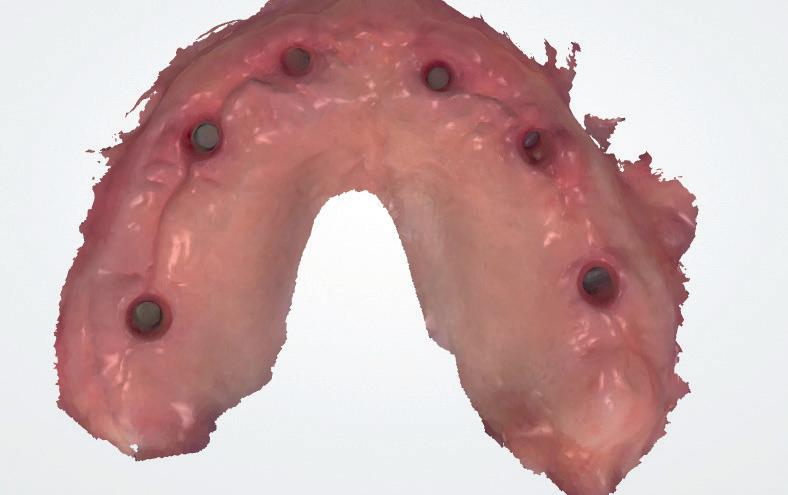

Om de implantaten op de juiste vooraf geplande positie te implanteren, zijn er een aantal mogelijkheden (afbeelding 1 en 2). Eén daarvan is om de chirurgie guided uit te voeren, maar dat is lastig omdat de guide niet op elementen afgesteund kan worden. De guide dient dan met guide pins vastgeschroefd te worden, maar dat heeft als nadeel dat bij verplaatsing van de guide de implantaten niet op de juiste positie staan. Bij immediaat implanteren kan tegenwoordig gebruikgemaakt worden van meerdere stac-

1. Edentate maxilla

kable guides, die op een base guide geklikt kunnen worden. Een tweede methode is om op basis van de CBCT-scan in de mond uit te meten waar de implantaat locaties zijn en door te kijken naar referentie van de onderkaak. In deze cases werd besloten om de implantaten vrij uit de hand te plaatsen.

7. Intraoraal scan occlusaal van de implantaten

8. Intraoraal scan met de scan

abutments

voor de implantaten (afbeelding 3). Hierna werd met een meetinstrument de locaties van de implantaten uitgemeten en werd een initiële osteotomie op deze locaties gemaakt. Voor de 16 werd een crestale sinusbodemelevatie met Densah boren uitgevoerd. Hierbij werd het zachte bot gecondenseerd om naar crestaal geduwd te worden, waarna het membraan van Schneider meelifte. Door de osteotomie werden 1cc botkorrels geplaatst en daarna direct het implantaat. Ter plaatse van de 14 zat een verticaal botdefect, na plaatsen van dit implantaat, werd de kaak verticaal verhoogd. Er werden 6 implantaten van het merk AnyRidge (MegaGen Implant Company, Korea) geplaatst met diameter 5.0 mm aan de distale zijdes, diameter 4.5 mm bij de premolaren en 4.0 mm implantaten bij de laterale incisieven (afbeelding 4).

Ter plaatste van de 16 en 14 werden verticale matrashechtingen geplaatst, waarna er één doorlopende hechtingen van tuber tot tuber volgde met een 4-0 gevlochten hechtdraad (afbeelding 5). Gedurende de eerste 2 weken van de genezing is het van essentieel belang voor de wondgenezing, dat de patient geen bovenprothese draagt. Deze werd daarom ingenomen, met de uitleg dat direct dragen van de bovenprothese een nadelige invloed heeft op de genezing van de kaak, de botopbouw en de implantaten. Patiënt kwam 2 weken na de chirurgie retour voor het verwijderen van de hechtingen, waarna de binnenzijde van de bovenprothese werd uitgeslepen en voorzien werd van een softliner als nieuwe tijdelijke voering voor retentie van de bovenprothese. Vanwege de kaakverhoging en sinusbodemelevatie, werd 6 maanden genezing afgewacht van het bot en integratie van de implantaten.

Tweede fase chirurgie

Na de genezingsperiode werd eerst een OPT röntgenopname vervaardigd om de genezing van de implantaten, kaakverbreding en sinusbodemelevatie te beoordelen. Er waren geen complicaties opgetreden. Bij de tweede fase chirurgie is het van absoluut belang dat er minimaal 2-3 mm gekeratiniseerd weefsel aan de buccale zijde van de implantaten wordt verkregen, anders kan de patiënt de implantaten niet goed reinigen en door de trekkrachten van de mucosa ontstaat al gauw peri-implantaire ontstekingen en recessies. De incisie hoeft niet van tuber tot tuber te zijn, maar 2 incisies van de 16 tot de 12 en 26 tot de 22 is voldoende, waarbij de incisie genoeg gekeratiniseerd weefsel aan de buccale zijde bevat, dat naar

de buccale zijde van de implantaten wordt geduwd. Er werden 6 healing abutments van 6 mm hoogte op de implantaten geplaatst, waarna de wonden werden gehecht met een 6-0 monofilament hechtdraad. In de prothese werd een nieuwe softliner over de healing abutments geplaatst. Het weefsel dient minimaal 4 weken genezingstijd te hebben (afbeelding 6).